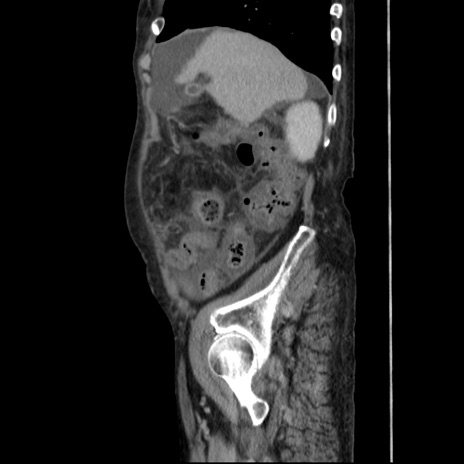

症例31(矢状断像)

【症例】80歳代 女性

【主訴】腹部膨満感

【現病歴】他院にて肝硬変にてフォロー中。1週間前から便秘、腹部膨満感、臍部腫瘤あり受診となる。

【既往歴】肝硬変

【身体所見】腹部膨隆あり、皮膚変化なし、疼痛なし。

【データ】WBC 4600、CRP 0.25